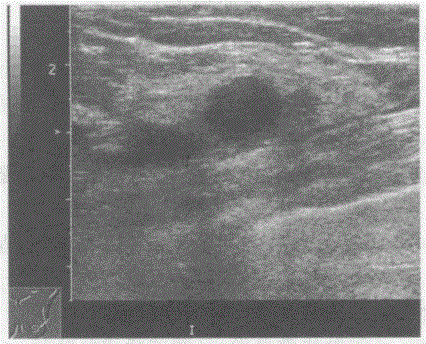

问题 临床资料:女,35岁,体检发现乳腺多发肿物,质软。 超声综合描述:双侧乳腺腺体层结构紊乱,内可见多个类圆形无回声区,边界整齐光滑,包膜完整,最大位于左乳外上象限,大小1.7cm×1.9cm,后方声加强及侧方声影,CDFI:内未见动静脉血流信号。 超声提示:

选项 A.乳腺癌 B.乳腺脓肿 C.乳腺囊肿 D.乳腺导管扩张

答案 C